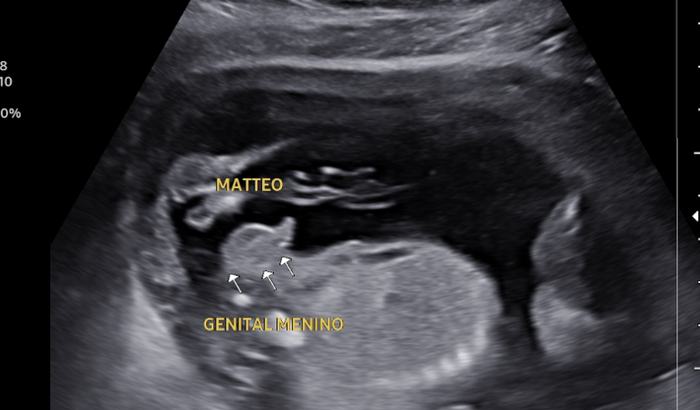

Olá! Me chamo Keila tenho 26 anos e sou a Mamãe do Matteo que ainda está em meu ventre.

No ano de 2018 fiquei grávida e infelizmente tive um aborto espontâneo que me deixou arrasada, ja tinha desistido de ser mae por conta da dor que passei. Porem, os anos se passaram e aqui estou em 2024 gravida do meu pequeno Matteo, meu bebe arco-ires. Estou com 6 meses de gestação e gostaria humildemente da ajuda de vocês para que eu pudesse montar o quartinho do meu pequeno que espero ansiosamente.